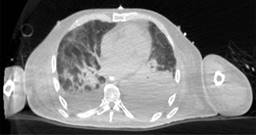

Paciente masculino de 69 años de edad con historia de diabetes mellitus tipo 2 en tratamiento con metformina y clorpropamida, hipertensión arterial en tratamiento con losartán y amlodipino. Se presenta al servicio de urgencias por mostrar cefalea, dolor torácico, tos, mialgias, artralgias y disnea de una semana de evolución. A su ingreso muestra frecuencia cardiaca 114 lpm, frecuencia respiratoria de 24 rpm, saturación de oxígeno de 80% sin apoyo de oxígeno suplementario, glucosa 587 mg/dl, leucocitos de 25,690 cel/mm3, neutrófilos 85%, linfocitos 1.2%, hemoglobina 16.3 g/dl, procalcitonina 3.78 ng/dl, gasometría arterial con pH 7.41, pCO2 21 mmHg, PO2 35 mmHg, HCO3 13 mmol/l, saturación de oxígeno 62%. Se realiza prueba rápida de antígeno para SARS-CoV-2 resultando positiva, tomografía axial computarizada (TAC) de tórax en la que se observan datos radiológicos sugestivos de infección por SARS-CoV-2 (Figura 1), se inicia manejo con oxígeno suplementario, bomba de infusión de insulina, carbapenémicos, antihipertensivos, dexametasona y profilaxis antitrombótica con enoxaparina. A las 48 horas de su ingreso continúa con choque séptico, se inician aminas vasopresoras, se realiza intubación orotraqueal y soporte con ventilación mecánica invasiva, se coloca sonda nasogástrica (SNG), la cual 24 horas posterior a su colocación reporta hematemesis acompañada de distensión abdominal, leucocitosis de 40,000 cel/mm3, se realiza TAC abdominopélvica simple, la cual revela neumatosis gástrica y neumoperitoneo (Figura 2), se efectúa laparotomía exploradora urgente encontrando necrosis de la curvatura mayor del estómago, se lleva a acabo gastrectomía vertical con engrapadora GIA cartuchos morados de 45 y 60 mm (Figura 3), se refuerza línea de grapeo con sutura continua prolene 00, se coloca sonda de yeyunostomía de alimentación a 60 cm del ángulo de Treitz y se dejan drenajes tipo Saratoga. A las 24 horas postoperatorias paciente reporta estabilidad hemodinámica y se suspenden aminas vasopresoras, se inicia nutrición enteral con dieta elemental. El quinto día postquirúrgico muestra adecuada tolerancia a dieta enteral por yeyunostomía, se realiza prueba con azul de metileno por SNG sin evidencia de fugas y descenso de leucocitos a 24,000 cel/mm3. Se recaba resultado de histopatología, el cual revela necrosis panmural asociada a trombosis arterial secundaria a microorganismos compatibles con Mucor sp., por lo que se inicia manejo con anfotericina B (Figuras 4 y 5). En el seguimiento muestra buena evolución, se realiza TAC abdominopélvica con contraste por SNG, la cual descarta fugas y colecciones intraabdominales y se corrobora integridad de la pared gástrica, se retiran drenajes y se da alta de cirugía general el día nueve postquirúrgico continuando manejo a cargo del servicio de medicina interna. Durante los siguientes días de hospitalización, el paciente presenta deterioro cardiovascular y pulmonar, se toma urocultivo, el cual evidencia crecimiento de Candida tropicalis, se realiza TAC de cráneo, tórax y abdominopélvica con contraste oral (Figuras 6 y 7), continúa sin evidencia de fugas a nivel abdominal, se descarta mucormicosis rinocerebral y pulmonar, se reporta probable neumonía bacteriana sobreañadida y neumopatía intersticial secundaria a COVID-19, persiste deterioro clínico y choque refractario, el paciente fallece a 29 días de su ingreso.

Figura 2: Tomografía axial computarizada abdominopélvica simple, en la que se observa neumatosis gástrica y neumoperitoneo.

La mucormicosis es una infección micótica invasiva con alta mortalidad, su incidencia ha aumentado en los últimos años debido al incremento de la población en riesgo de infección y la mejora en las herramientas diagnósticas. Fue descrita por primera vez a nivel pulmonar en 1876 por Furbringer.5 Ocurre principalmente en el contexto de un paciente inmunocomprometido.1 La mortalidad varía de 32 a 70%, la infección localizada se asocia con mejor supervivencia,6 se diagnóstica ante-mortem sólo en 25% de los casos. En su revisión de 31 casos, Dioverti y colaboradores reportan predominio en el sexo masculino (61%) y edad media de 47 años, 52% de los casos eran pacientes postrasplantados de órgano sólido y 35% pacientes en quimioterapia por neoplasia hematológica maligna, 100% de los pacientes presentaba al menos una comorbilidad, siendo la neutropenia la más común.2 Se ha descrito en pacientes con desnutrición severa, uso de corticoides, pero también en pacientes sin ningún factor predisponente.7 En nuestro caso el paciente tenía múltiples factores de riesgo ya descritos, la diabetes mellitus tipo 2 descompensada, la infección aguda por coronavirus y la terapia con esteroides que se inició para el manejo de COVID-19, como único factor que mejoraba el pronóstico se encontró la infección focal en estómago. La enfermedad se caracteriza por presentar vasculitis necrosante extensa con trombosis arterial e infarto tisular1 y presencia patognomónica de hifas ramificadas no septadas en ángulo recto en los tejidos,8 el género Rhizopus es el género que con más frecuencia se aísla.9 Entre los factores de riesgo conocidos se encuentra la hiperglucemia y la acidosis, ya que causan disfunción leucocitaria de neutrófilos y/o macrófagos afectando su quimiotaxis.10 Seis diferentes síndromes clínicos pueden presentarse, la infección rino-órbito-cerebral y la infección pulmonar son las más frecuentes y la gastrointestinal la menos común. Ésta se adquiere a través de la ingesta de alimentos contaminados o en el caso de cuidados asociados a la salud a través de dispositivos contaminados1 el estómago es el sitio más común de afección seguido del colon, intestino delgado y esógafo.11 La mayoría de los síntomas son inespecíficos, lo cual retrasa el diagnóstico y aumenta la mortalidad.2 La presentación clínica puede ser con dolor abdominal (68%), hemorragia gastrointestinal (48%), fiebre (19%) o cambios en la defecación (10%).2 A su ingreso el paciente no reportaba ninguna sintomatología a nivel abdominal, por lo que no existió ninguna sospecha de afección gastrointestinal, posteriormente se realizó sedación intravenosa e intubación orotraqueal siendo así imposible que el paciente manifestara afección a nivel gástrico, como único signo el paciente presentó hematemesis a las 24 horas de colocación de la SNG, lo cual descarta la posibilidad de una mucormicosis asociada a los cuidados de la salud, ya que 24 horas no son suficientes para lograr la introducción, inoculación y crecimiento del hongo, esto abre la hipótesis de que el paciente adquirió la infección micótica en su comunidad. El diagnóstico se puede sospechar por hallazgos endoscópicos, los cuales pueden ser una masa fúngica o lesiones necróticas que cubren áreas ulceradas que pueden perforarse y causar peritonitis.2 A menudo se inicia el protocolo de estudio ante la presencia de un absceso intraabdominal, el diagnóstico se puede efectuar mediante biopsia del área sospechosa durante la cirugía o endoscopia,7 pocas muestras son enviadas a cultivo2 y las que se envían son positivas sólo en 30%, además se requieren medios de cultivo especializados como agar papa dextrosa para favorecer el crecimiento de los hongos,12 se requieren además pruebas moleculares confirmatorias que pudieran detectar antígenos de superficie, los cuales aún no están disponibles.2 Los hallazgos por tomografía pueden ser los siguientes: engrosamiento focal o difuso de la pared gástrica, neumatosis con realce disminuido en la pared a la administración de contraste (gastritis enfisematosa) secundaria a la isquemia y necrosis, colecciones adyacentes, necrosis de la pared con disrupción focal o perforación y rara vez neumoperitoneo.13 Al presentar hematemesis estamos conscientes de que el siguiente paso diagnóstico podría haber sido una endoscopia digestiva alta, pero la distensión abdominal que presentaba el paciente sugería alta probabilidad de perforación de víscera hueca, por lo que inicialmente se realizó TAC de abdomen. Al reportar neumatosis gástrica y neumoperitoneo, se consideró una urgencia quirúrgica descartando la toma de endoscopia en ese momento, la laparotomía exploradora (LAPE) permitió la exploración directa del estómago y la resección parcial del mismo como medida diagnóstica y terapéutica. El tratamiento consiste en antifúngico y desbridamiento quirúrgico urgente, ya que la presencia de tejido necrótico afectará la penetración del antifúngico a los tejidos, además de lo anterior se deberá proporcionar soporte médico agresivo de las comorbilidades.14 La anfotericina B liposomal intravenosa es el tratamiento de elección, ya que ha demostrado ser más eficaz que la anfotericina B convencional,15 el retraso en el inicio de la anfotericina más de seis días aumenta al doble la mortalidad.4 A pesar de que la mayoría de la bibliografía sugiere el tratamiento quirúrgico agresivo, optamos por un tratamiento más conservador al preservar una porción del estómago efectuando solamente una gastrectomía vertical, ya que a la inspección macroscópica se presentaba delimitación clara entre el tejido necrótico y el tejido viable. Consideramos que el tratamiento quirúrgico que efectuamos fue acertado, puesto que en el seguimiento posquirúrgico el paciente mostró buena evolución, la prueba con azul de metileno y las dos tomografías de abdomen con contraste en estómago a través de SNG nos permitieron comprobar la integridad de la línea de sutura desde su primer día postquirúrgico y hasta el día de su fallecimiento, la muestra enviada a patología permitió efectuar el diagnóstico y así iniciar la terapia dirigida con anfotericina B, y ya que no se demostró afección fúngica por Mucor sp. a otro nivel orgánico, se atribuye la causa de muerte a las complicaciones infecciosas nosocomiales a nivel pulmonar y urinario.